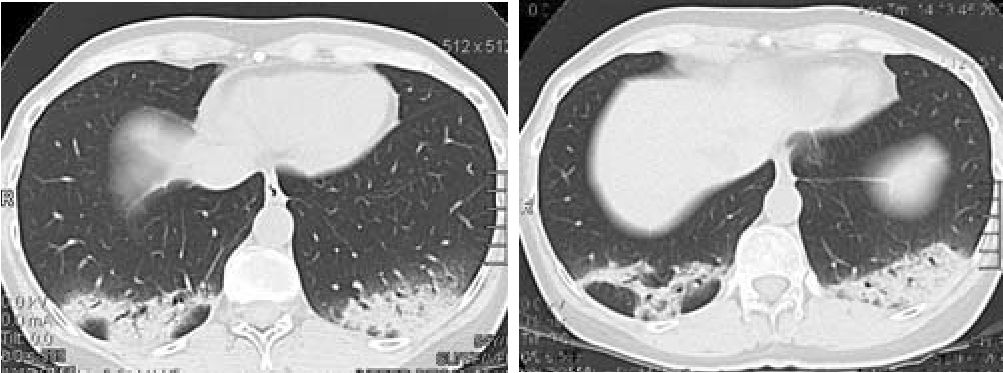

Рис 1. Рентгеновская компьютерная томография 08.07.10. Аксиальная проекция.

В заднебазальных отделах легких в проекции S8-S 10 определяется неоднородное уплотнение легочной ткани с визуализируемыми просветами бронхов, широко прилежащее к висцеральной плевре.

Спустя 2 нед. от начала лечения наблюдалась дальнейшая положительная динамика: отсутствие жалоб, уменьшение СОЭ до 42 мм/ч, при контрольной КТ грудной клетки - уменьшение размеров и плотности инфильтратов в легких (рис. 6).

Рис 6. Рентгеновская компьютерная томография 29:07.10 Аксиальная проекция.

Через 2 недели стероидной терапии выраженная положительная динамика в виде значительного уменьшения выраженности, размеров и интенсивности выявляемых ранее изменений.

Еще через 2 мес. инфильтрация в ткани легких уже не определялась (рис. 7), СОЭ - 30 мм/ч, СРБ - 4 мг/л.

Рис. 7. Рентгеновская компьютерная томография 08.10.10 Аксиальная проекция.

Через 2 месяца полный регресс ранее выявляемых изменений.